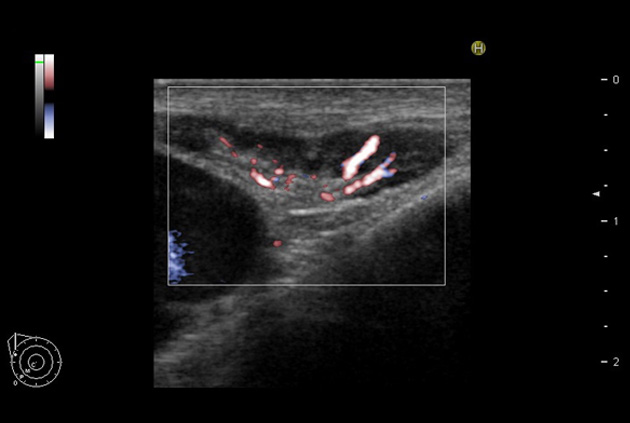

Directional eFLOW (D-eFLOW)

Displays blood flow with directional information at higher frame rates and spatial resolution compared to conventional methods. Detail and accuracy of blood flow information is greatly increased with reduced blooming of color.